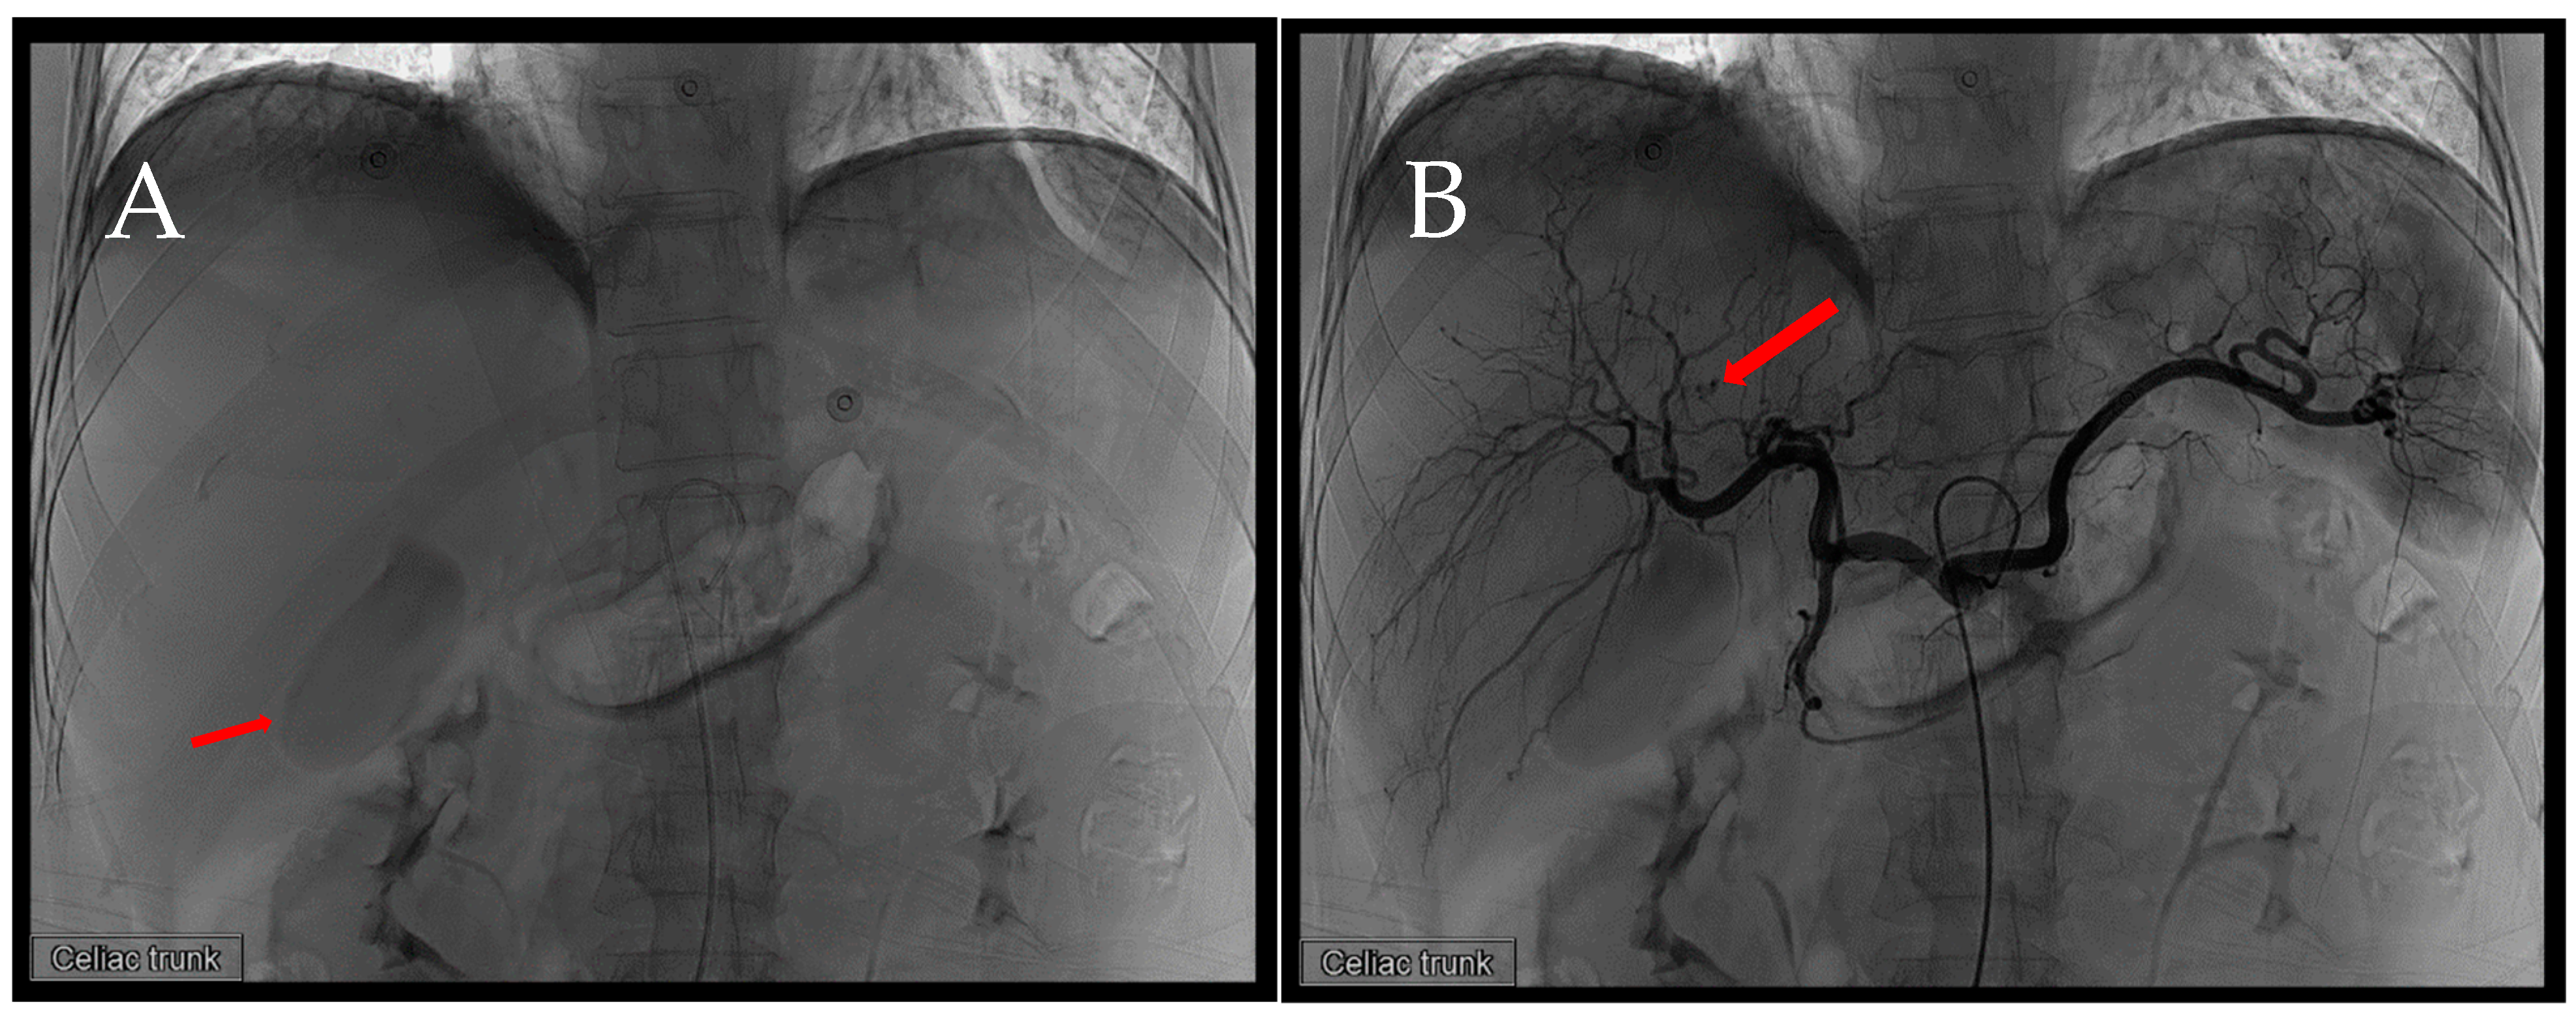

Figure 2. First TAE. After accessing the celiac trunk using a 4Fr. RH catheter, we performed a series of angiographies. (A) Prior to contrast injection, an evident hyperdense lesion (arrow) corresponding to the location identified in the CT scan is observed. The increased density is likely attributed to contrast extravasation during the preceding CT, thereby manifesting on this image. (B) A distinct extravasation (arrow) is visible, but its location does not align with the previously identified position in the CT scan.